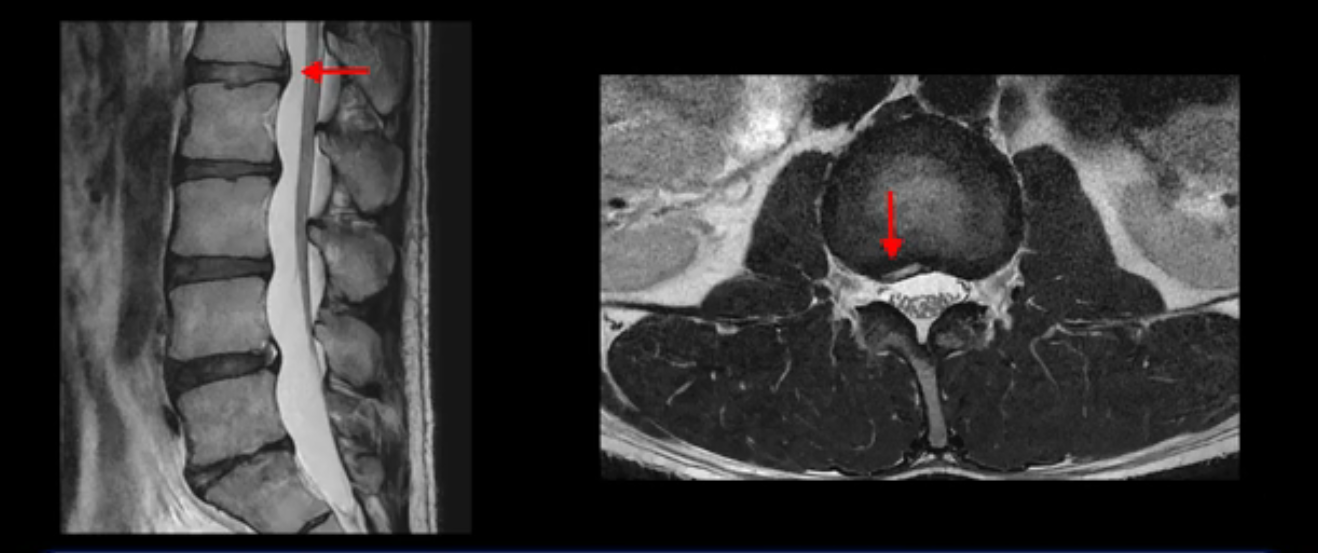

그런데 이분의 증상과 MRI가 전혀 일치하지 않는데, 왜 그런지 지금부터 자세히 설명드립니다. 이분 증상은 앉으면 엉치와 허리가 심하게 아파 10분 이상 앉는 게 어렵고 양쪽 발가락이 앉아있을 때나 누워있을 때 다 저립니다. 걸을 때도 아파서 10분 걷기도 어렵습니다. MRI를 마디마디 살펴보면 1번 2번은 오른쪽으로 살짝 밀려나온 디스크가 있지만 전혀 심하지 않고, 뒤에 또 설명하겠지만 최근에 밀려나온 급성 디스크가 아니고 오래된 디스크로 판단됩니다.

2번 3번도 비교적 디스크 상태는 좋고 신경 구멍 넓이도 아주 넓습니다.

5번 1번 역시 가운데로 디스크 조금 밀려 나와있지만 신경 공간 넓이는 아주 넓어서 신경 눌림 있을 거라고 예상이 안됩니다.

추간공도 보시다시피 왼쪽, 오른쪽 전부 다 매우 넓어서 신경이 눌릴만한 부분이 전혀 보이지 않습니다.

앞서 1번 2번, 4번 5번, 5번 1번의 디스크가 찢어지고 조금 밀려 나온 게 최근에 찢어진 게 아니고 오래된 걸로 보인다고 말씀 드렸죠. 왜 그럴까요? 만약 급성으로 찢어진 것이라면 아주 심한 디스크성 통증이 있겠죠. 기침이나 재채기를 하면 심하게 아프고 허리를 조금만 구부리거나 비틀면 아주 날카로운 통증들이 생길 겁니다. 그런데 이분은 이런 증상이 전혀 아닙니다. 또 디스크의 밀려나온 정도도 전혀 심하지 않기 때문에 이분이 가지고 계신 양쪽 다리 저림, 특히 이분은 누워있을 때도 양쪽 발이 발가락까지 쑤신다고 하는데 이정도 디스크 때문에 그런 증상은 생길 수가 없는 겁니다. 이처럼 이분의 가벼운 디스크 탈출은 이미 오래 전에 진행되었고 섬유륜 자체는 이미 아문 상태인데도 디스크내장증을 진단받은 환자들 중에는 본인이 섬유륜 파열 환자라고 끝까지 믿는 분들이 많습니다. 다시 말하지만 디스크내장증이라는 진단을 받은 환자들을 보면 거의 전부 다 섬유륜 파열 증상이 아닙니다. 증상이 완전히 다릅니다. 진단이 애초에 잘못되면 어떤 치료를 받아도 좋아질 수 없습니다.